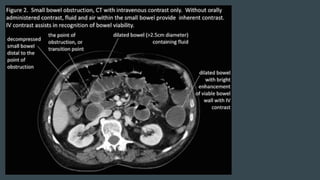

CT SCAN

PRESENCE OF OBSTRUCTION

LOCATION, SEVERITY, AND

CAUSE

CT SCAN PRESENCE OFOBSTRUCTION LOCATION, SEVERITY, AND CAUSE